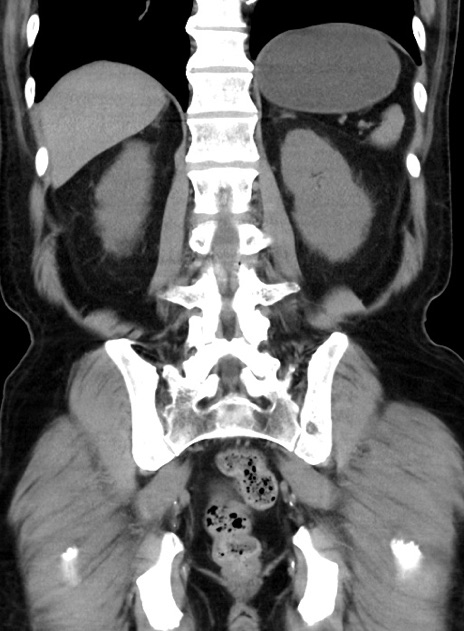

横断像

【症例】70歳代 男性

【主訴】腹痛・嘔吐

【現病歴】昨晩より、嘔吐・腹痛あり。今朝になっても嘔吐あり。来院。

【既往歴】心臓バイパス手術、開腹胆摘、腸閉塞

【身体所見】BP 107/71mmHg、HR 116/min、腹部:平坦、軟、下腹部に軽度圧痛あり。反跳痛なし。

【データ】WBC 15100、CRP 0.32